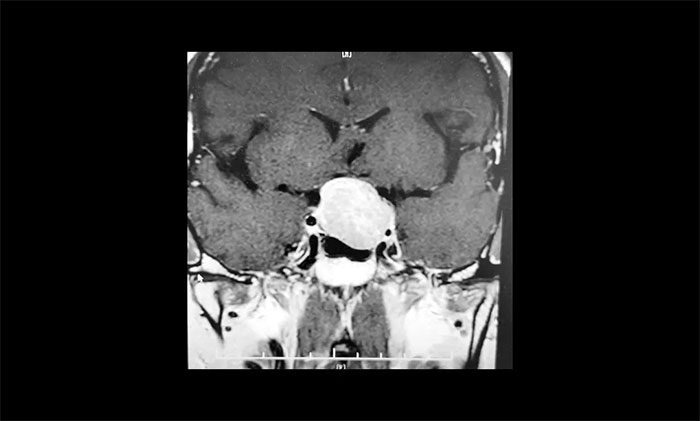

今年38歲的張先生,是江蘇人。去年9月份開始,自感左眼視力下降、視物不清,在當(dāng)?shù)蒯t(yī)院眼科檢查,左眼視力測(cè)不出,外側(cè)視野缺損,查不出病因。今年2月中旬,在另一家醫(yī)院檢查,經(jīng)頭顱MRI檢測(cè),發(fā)現(xiàn)垂體巨大占位,考慮為垂體腺瘤。

▲ 腫瘤侵襲生長(zhǎng),包繞左側(cè)海綿竇

為求進(jìn)一步確定病情,張先生在家人陪伴下,慕名來(lái)到上海藍(lán)十字腦科醫(yī)院。經(jīng)鞍區(qū)MRI平掃+增強(qiáng)顯示:蝶鞍顯著擴(kuò)大,鞍底下陷,垂體窩見(jiàn)類橢圓形異常信號(hào),大小約3.1×2.7×2.1cm,病變向鞍上生長(zhǎng),推移視交叉上抬,與左側(cè)海綿竇分界欠清晰,被包裹1/2。

神經(jīng)外科6B病區(qū)專家李士其教授、潘仁龍主任、吳治群博士會(huì)診后,考慮為侵襲性垂體巨腺瘤,乒乓球大小的瘤體壓迫視神經(jīng),并且侵襲生長(zhǎng),左側(cè)海綿竇部分受包繞,向上已突破鞍隔,壓迫視神經(jīng)、視交叉、下丘腦。如果腫瘤進(jìn)一步生長(zhǎng),可能加重視力下降、甚至失明。